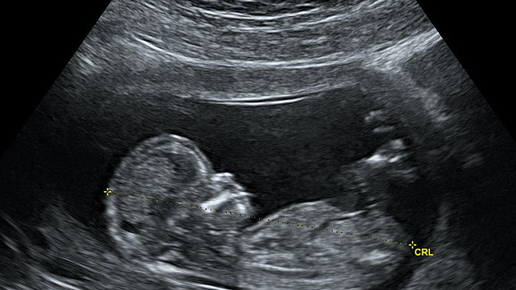

«Насть, у меня для тебя не очень хорошие новости», - сказала мне моя врач-гинеколог на очередном приеме. «Пришли результаты скрининга. У тебя высокий риск синдрома Дауна» У меня подкосились ноги. Как так? На УЗИ все было хорошо, без патологий, какой риск?! Врач, как могла, меня успокаивала. Поделилась своей историей, ей тоже ставили риск СД, но - из-за возраста. У меня же был очень повышен какой-то показатель по крови. В общем, врач посоветовала мне не переживать раньше времени, сказав, что сейчас почти каждой второй беременной ставят такой риск и он не подтверждается...